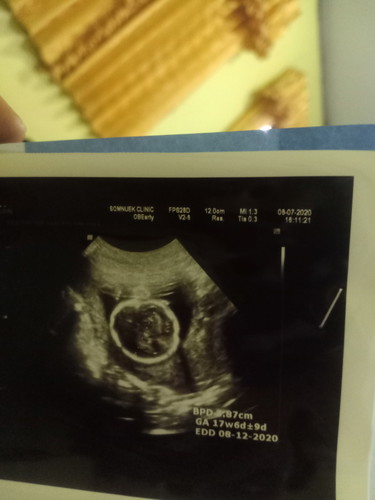

17w6dไปอัตราซาวมาคะน้องเป็นผู้หญิงแต่คุณหมอบอกหัวน้องอยู่ต่ำมากรู้สึกหนักหน่วงตรงท้องน้อยคะบางทีนูนขึ้นเห็นชัดเจน จะไห้หมอบ้านแต่งท้องไห้ดีมั้ยคะ